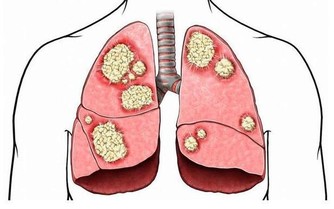

猝死主要分為三類導致猝死的情形有許多種,大多與心臟有關,叫心源性猝死,另有腦幹出血、中暑等其他原因也會導致很短時間內死亡。

一般心源性猝死分三種:

一種是器質性心髒病,最常見的是冠心病。多發生在年齡稍大的男性身上,他們多伴有糖尿病、高血壓等慢性疾病,同時愛抽煙,長得胖,特別是在激動狀態下容易發生胸悶胸痛,引發猝死,還會在運動、生氣、氣溫驟降的情況下發生;

第二種是應激性心髒病,這常發生在年輕女性身上。其致病機理是突然受到刺激後,馬上分泌出大量腎上腺素,導致心臟劇烈顫動致死。

第三種是遺傳性心髒病,也就是心律失常。這種病很多人不知道自己是否患有,在應激情況下也會導致死亡。